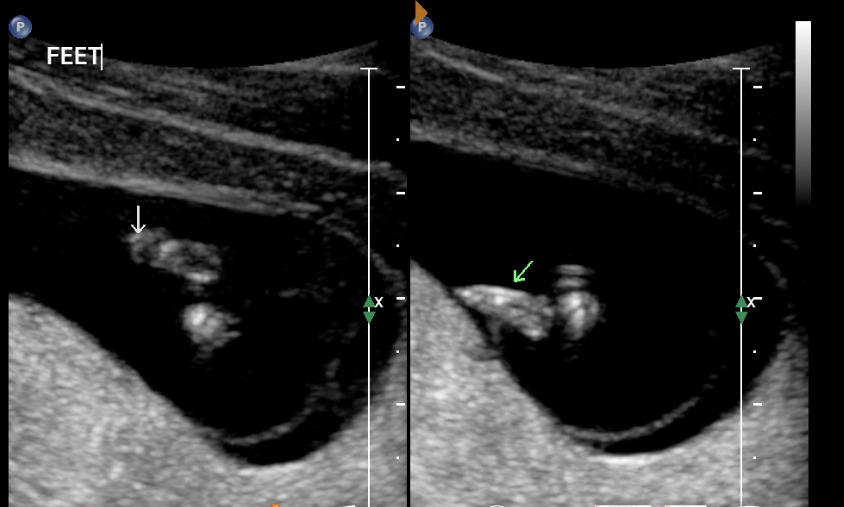

We got into the scan. And as soon as she put the scanner on my belly, I saw it. I knew this was real. Our little baby was tiny (1cm) but alive- she could see it's heartbeat! Our little baby was 7 weeks old.

![]() |

At 9 weeks I went for another scan. I had been bleeding a bit, and so again was fearful about what they might find. But again, I saw a lovely baby and a strong heartbeat. This time I was able to see baby wriggling around! Which was so amazing. I have a picture, but it is a bit blurry.

| The head is at the left, the body is the C shaped looking blur in the middle of the screen. |

And then- boom- at 11 weeks 4 days I started bleeding quite heavily. It went on for several days, and it really stressed me out. At times I really believed it was the end, and I was so upset. It was a good thing my scan was only a few days later. Going into the scan, again I didn't know what to think. I didn't know whether to hope. But amazingly, all was ok! Matt and I were so relieved/thankful/awe-struck/happy and all those good emotions at once.

| I know this looks like just another baby scan to you, but this is the best photo ever to me! |

| Little baby feet! Oh, they kill me. Already wanna kiss them. |